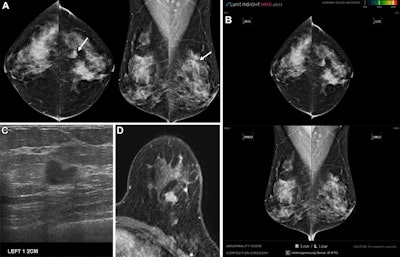

Images in a 42-year-old asymptomatic woman. (A) Digital mammograms show an irregular spiculated mass in the left upper outer quadrant (arrows). (B) Artificial intelligence (AI) software did not mark this lesion due to a low abnormality score. (C) Ultrasound and (D) breast MRI scans revealed a 1.1-cm irregular mass in the left upper outer breast at the 1-o'clock position. Breast-conserving surgery was performed; the lesion was confirmed as a 1.1-cm invasive ductal carcinoma (luminal subtype, histologic grade 3) without axillary lymph node metastasis. The lesion was classified as actionable; three radiologists categorized it as suspicious. The reason for the AI miss was that the lesion was obscured by overlying dense breast tissue. CC = craniocaudal, MLO = mediolateral. Images and caption courtesy of the RSNA.Images in a 42-year-old asymptomatic woman. (A) Digital mammograms show an irregular spiculated mass in the left upper outer quadrant (arrows). (B) Artificial intelligence (AI) software did not mark this lesion due to a low abnormality score. (C) Ultrasound and (D) breast MRI scans revealed a 1.1-cm irregular mass in the left upper outer breast at the 1-o'clock position. Breast-conserving surgery was performed; the lesion was confirmed as a 1.1-cm invasive ductal carcinoma (luminal subtype, histologic grade 3) without axillary lymph node metastasis. The lesion was classified as actionable; three radiologists categorized it as suspicious. The reason for the AI miss was that the lesion was obscured by overlying dense breast tissue. CC = craniocaudal, MLO = mediolateral. Images and caption courtesy of the RSNA.